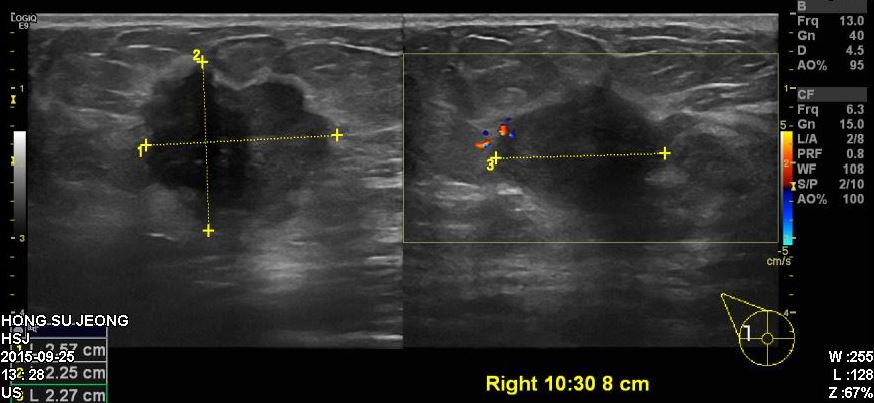

우측유방에 만져지는 멍우리 내원하신 40대 환자분이십니다.

본원에서 우측 10시30분 방향에 혹을 조직검사 시행하였고

결과상 침윤성유관암으로 진단되었습니다.